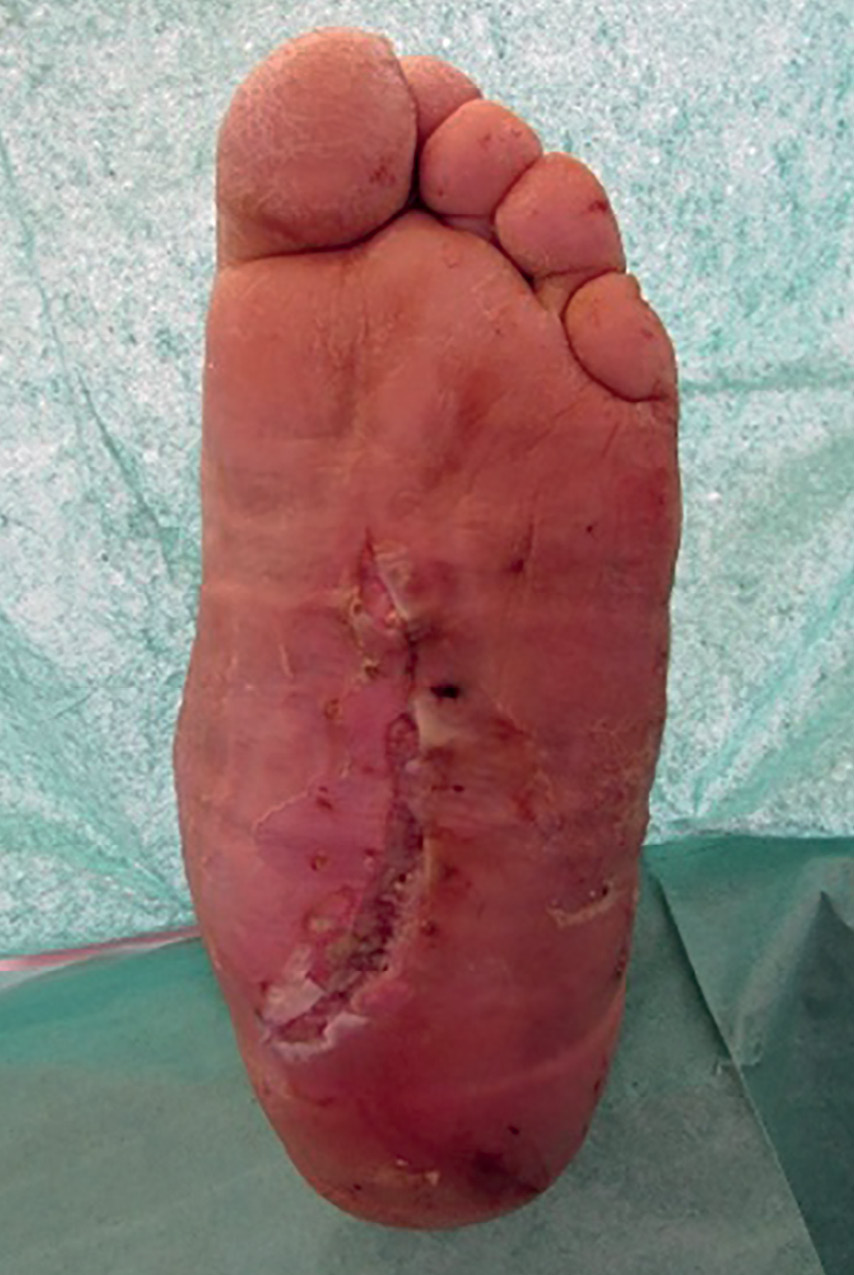

Рисунок 1. Внешний вид стопы до операции.

Работа выполнена с применением методов статистической обработки результатов анкетирования (табл. 1). Были проанализированы данные 55 пациентов, прооперированных в отделении диабетической стопы ФГБУ «НМИЦ эндокринологии» Минздрава России в 2009–2019 гг. Материалы исследования включали данные телефонного опроса, проводимого врачом среди пациентов. Все данные вносились в специально разработанную авторами анкету. Всем пациентам под проводниковой или спинномозговой анестезией была проведена реконструктивная операция, направленная на коррекцию грубой деформации среднего отдела стопы, — резекция пролабирующих костей предплюсны (кубовидной и клиновидных). Этапы лечения пациента с деформацией среднего отдела стопы при ДНОАП приведены ниже (рис. 1–3).